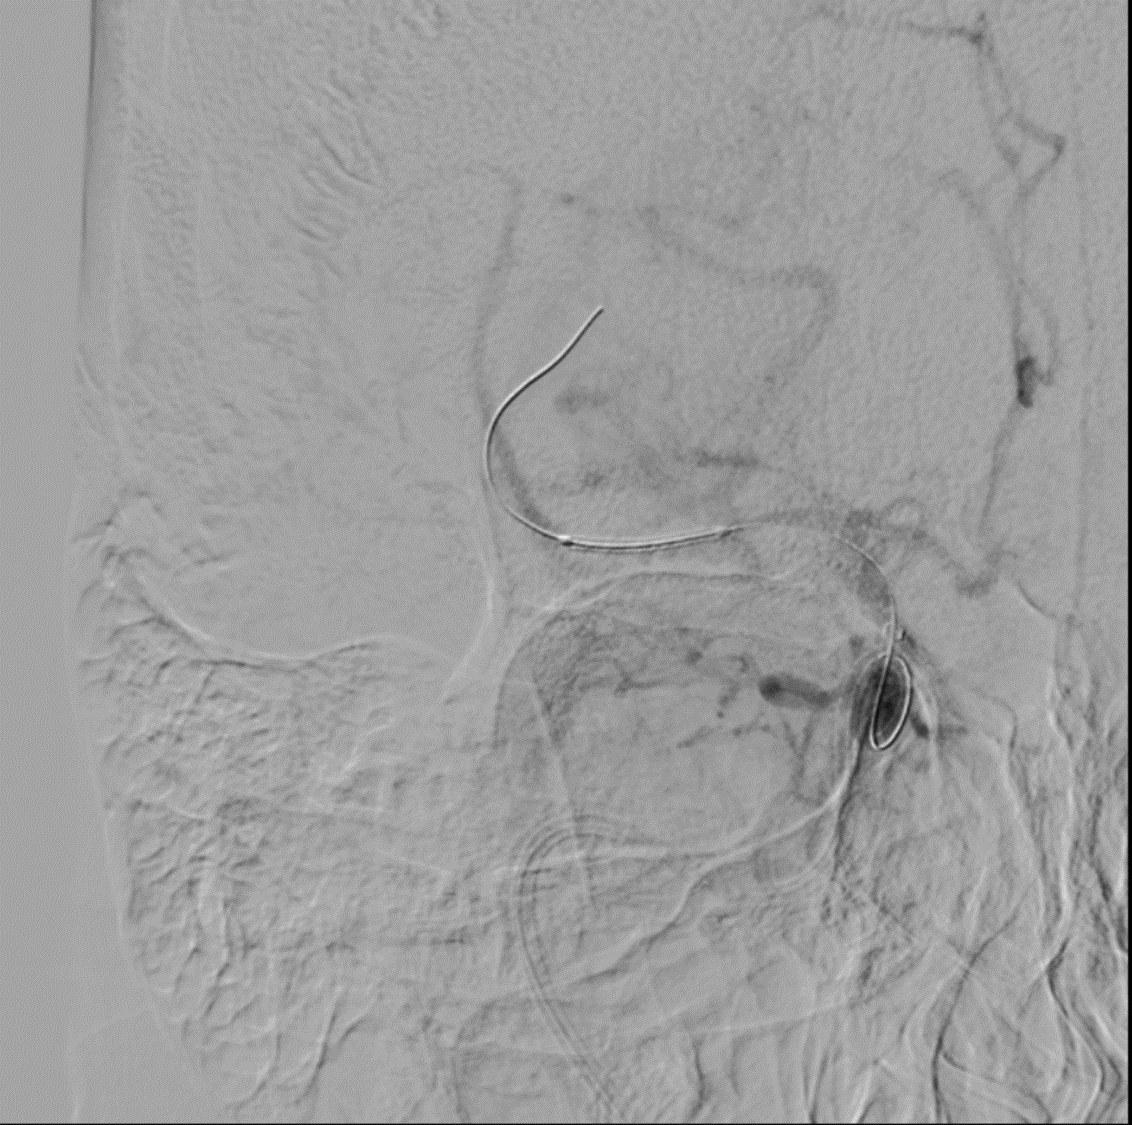

Tight stenosis opened up with a Balloon mounted stent and final result